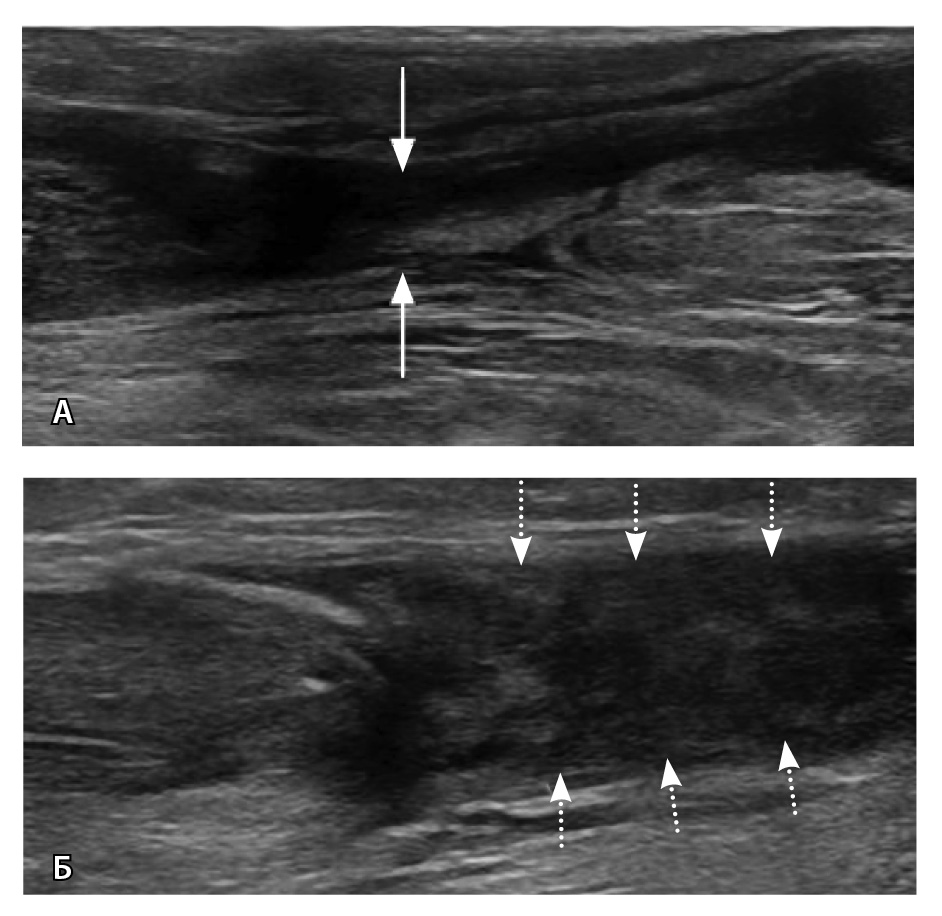

По данным N. El-Liethy и H. Kamal чувствительность сонографии в диагностике повреждения ахиллова сухожилия и сухожилия задней большеберцовой мышцы составила 100%, при этом в последующем результаты подтвердились при помощи МРТ. Существует мнение, что с помощью УЗИ удается классифицировать повреждения ахиллова сухожилия (рис. 6) аналогично МРТ в отношении тендинопатии, частичного повреждения и полного разрыва [58].

Рис. 6. Ультразвуковая диагностика голеностопного сустава: А – неполнослойный разрыв ахиллова сухожилия в области мышечно-сухожильного перехода (стрелки); Б – дефект 90% волокон, заполнен геморрагическим содержимым (пунктирные стрелки). Диастаз волокон, гематома